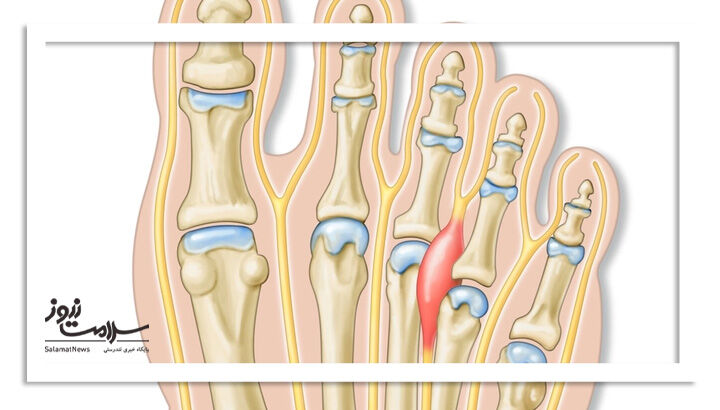

نوروم مورتون

این مشکل زمانی رخ میدهد که بافت اطراف یک عصب در جلوی پا ضخیم میشود. نوروم مورتون بیشتر بین انگشتان سوم و چهارم اتفاق میافتد و با کفشهای تنگ و پاشنه بلند تشدید میشود.